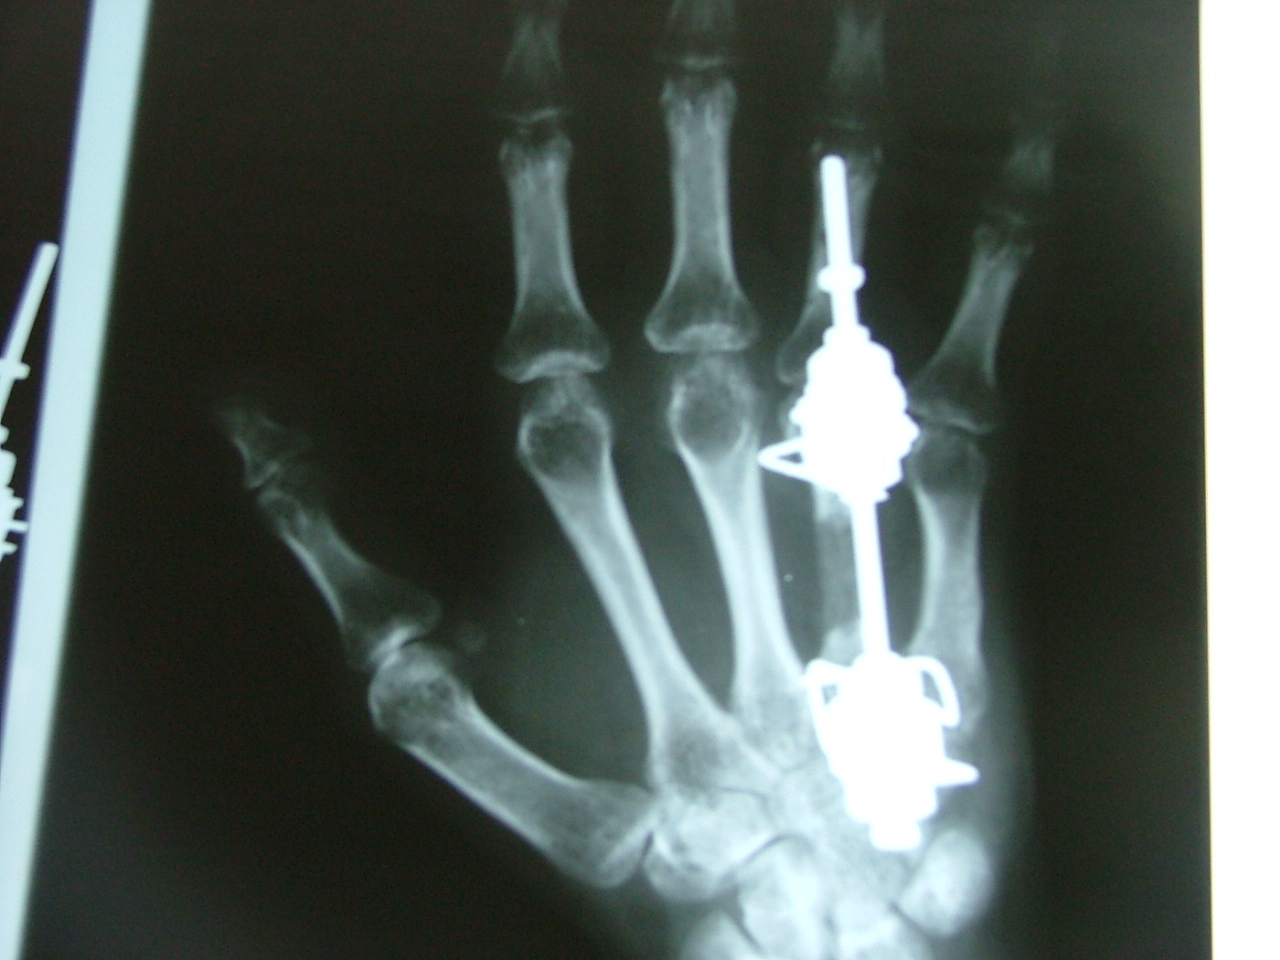

تهیه و تامین تجهیزات ارتوپدی و مشارکت در انجام اعمال جراحی ارتوپدی و عمل‌های نادر عضو تیم جراحی افزایش قد -جهت ترمیم شکستگی های قدیمی و جوش نخورده گی ها -طویل کردن اندامها- طویل کردن انگشت قطع شده - تعویض مفصل لگن _تعویض مفصل زانو _ بازسازی رباطACLوPCL_اصلاح ناهنجاریهای مادر زادی -با همکاری پزشکان و متخصصان مجرب آموزش دیده در روسیه و اتریش و سوئیس بروش جراحی ایلیزاروف و lon و lsa و واگنر و اسلایدینگ نیز جدید ترین روش افزایش قد و اندام در سال 1397 بنام hil هیل برای اولین بار- افزایش قد به 6 روش جراحی و جدیدترین روش در اروپا و روسیه. آدرس مطب _تهرانسر بلوار اصلی مجتمع سهند طبقه4 واحد 410